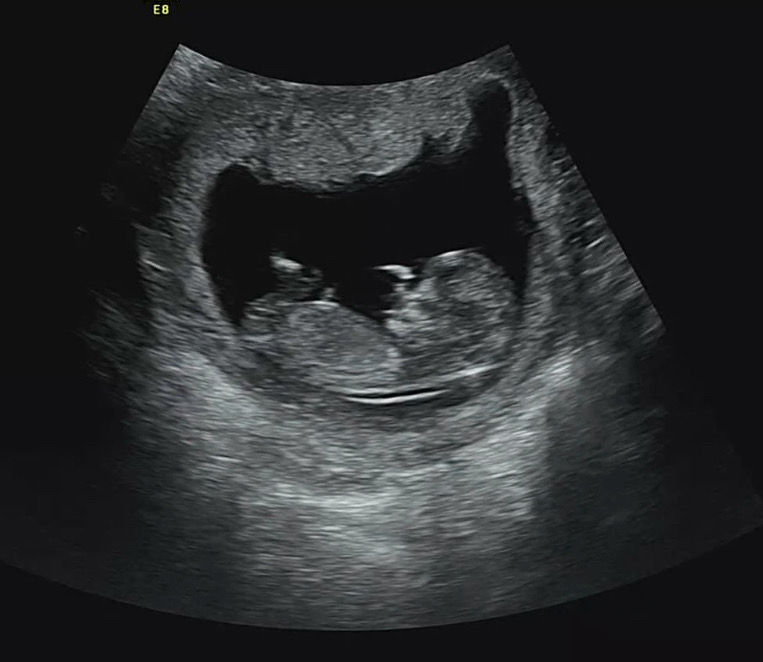

각도법으로 성별 예측부탁드려요🙏🏻❤️

12주 입니당